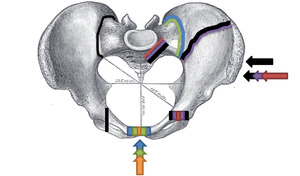

Superior view, Pelvic Fracture Types (2006). Force and break are shown by matching color: Anteroposterior compression type I (orange), Anteroposterior compression type II (green), Anteroposterior compression type III (blue); Lateral compression type I (red), Lateral compression type II (purple), F. Lateral compression type III (black). Increased force and breaks are shown by increasing size.

This fracture is best viewed anteriorly, while the other fractures are viewed superiorly. The arrow indicates where the force is coming from, and the colored lines indicate where the break occurs.

The Young-Burgess classification system is based on mechanism of injury: anteroposterior compression type I, II and III, lateral compression types I, II and III, and vertical shear,[5] or a combination of forces.